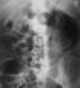

Emphysematous pyelonephritis